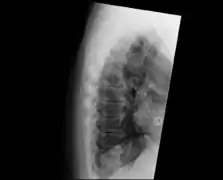

Confluent ossification of multiple contiguous vertebral bodies in diffuse idiopathic skeletal hyperostosis (DISH)